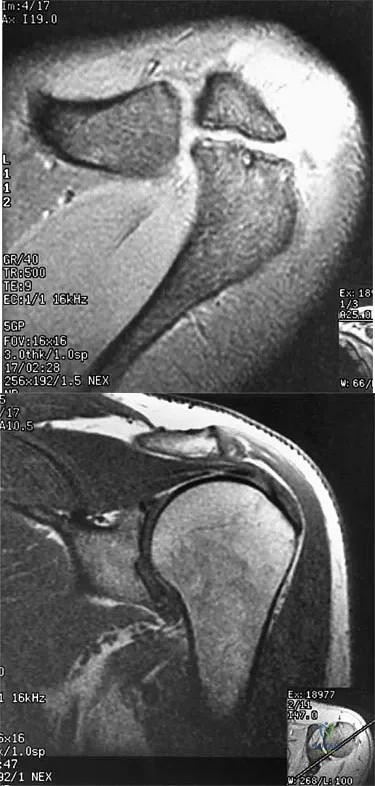

Figures 36a and 36b show the MRI scans of a patient who has shoulder weakness. What is the most likely diagnosis?

Explanation

Figure 4a shows the radiograph of a 20-year-old man who has an injury to the right shoulder. Figure 4b shows an arthroscopic view (posterior portal). The arrow points to a

Explanation

A 47-year-old male tennis player has pain in his nondominant shoulder that has failed to respond to 4 months of nonsurgical management. Examination reveals acromial tenderness and pain at the supraspinatus tendon insertion. He has a positive impingement sign, pain on forward elevation, and minimal cuff weakness. The MRI scans are shown in Figures 30a and 30b. To completely resolve his symptoms, treatment should consist of

Explanation